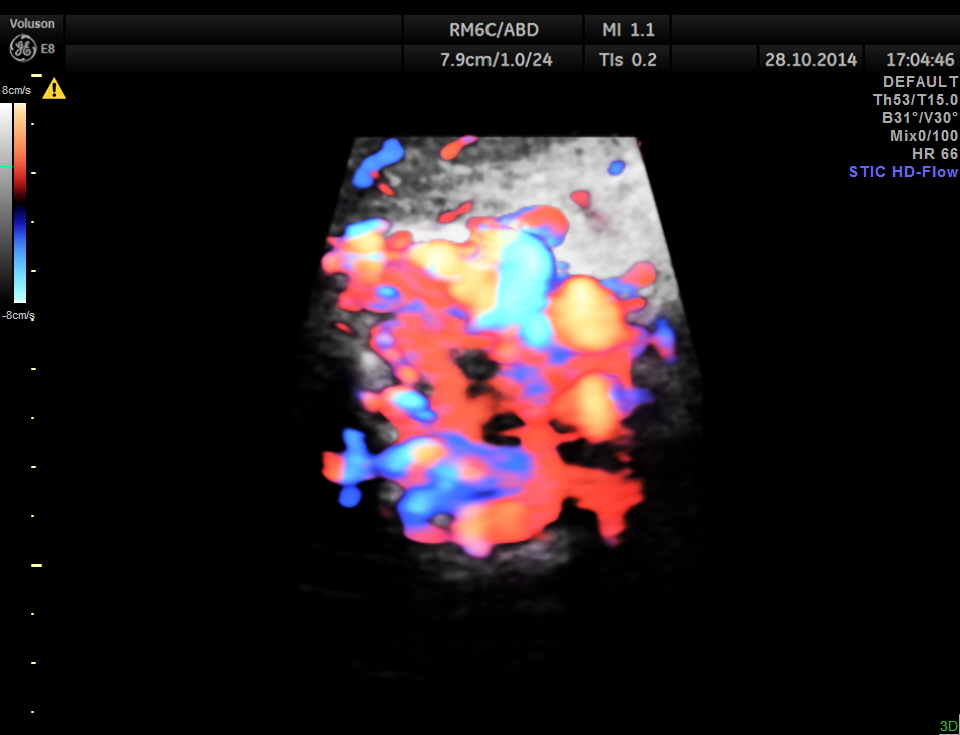

STIC HD flow image.

Main portal vein show flow reversal ( blue colour ) – centri-fugal flow suggestive of portal hypertension.